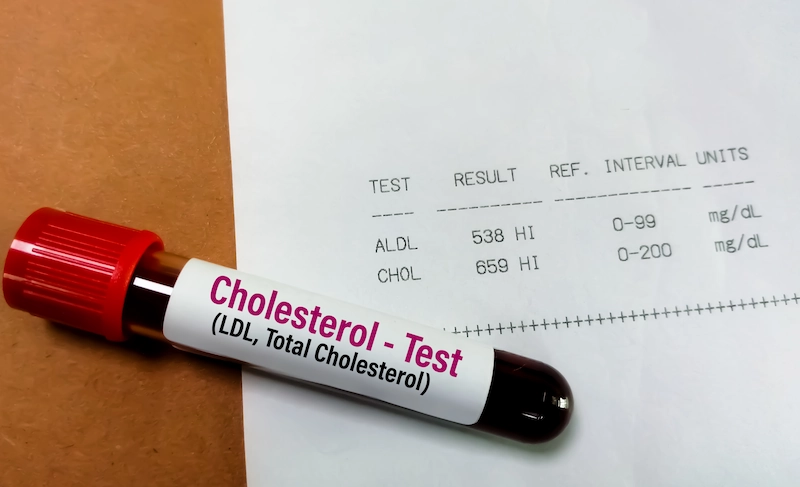

Kolesterol LDL: Definisi, Penyebab, dan Cara Menurunkannya

Kolesterol LDL adalah jenis kolesterol jahat yang perlu Anda waspadai. Kolesterol ini bisa menyebabkan beberapa penyakit, seperti hipertensi, stroke, jantung koroner, dan sebagainya. Maka dari itu, penting untuk selalu memperhatikan kadar kolesterol dalam tubuh Anda. Menurut dokter dari Enesis Group, dr. Shabrina Ghassani Roza, kolesterol jahat (LDL) dapat diturunkan dengan perubahan gaya hidup, seperti pola […]